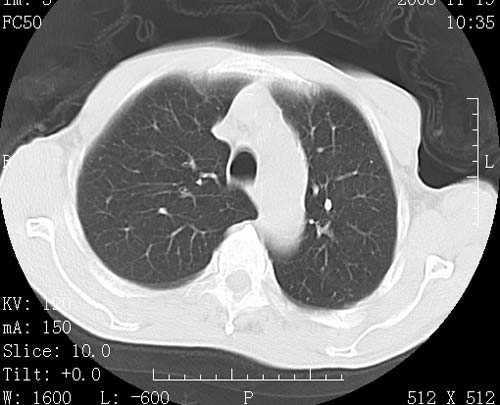

术前查体,双肺部结节是转移?结核?请点评

1)符合食管癌表现。2)两肺及纵隔淋巴结多发性转移瘤。3)左肺上叶舌段及两肺下叶炎症感染。

1)符合食管癌表现。2)两肺及纵隔淋巴结多发性转移瘤。3)左肺上叶舌段支气管扩张伴感染.

食管癌伴双肺转移,评述:肺部毛细血管网丰富,全身血液均快速流经肺部,癌细胞容易过滤定植,形成转移瘤,影象特点为以毛细血管末梢为中心的结节灶,边缘光滑锐利,少见有中心空洞着,不同来源的转移瘤可有各自特点,如甲状腺癌为双肺弥漫性微结节,本例有原发灶,双肺影象灶典型,左肺舌段条带状网格样伴胸膜天幕征,可视为癌性淋巴管炎。

左肺舌段有斑点钙化灶,能否说明是结核而不是转移?如果是转移将放弃手术改成化疗,如果是结核将考虑择期手术